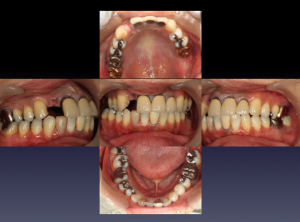

症例⑤

上左右の奥歯を失ってしまったため、保険の入れ歯を入れたが、違和感が強く、しっかり噛むことができないため、インプラントを併用した入れ歯を作ることで違和感なく、しっかり噛むことができるようになった。 また通常の入れ歯は、はずれないようにするため金属のバネを歯に引っ掛けるため見た目も悪いが、インプラントによって固定されているためバネもなく、見た目も非常に良いものとなっている。

術前レントゲン写真

-

術後レントゲン写真